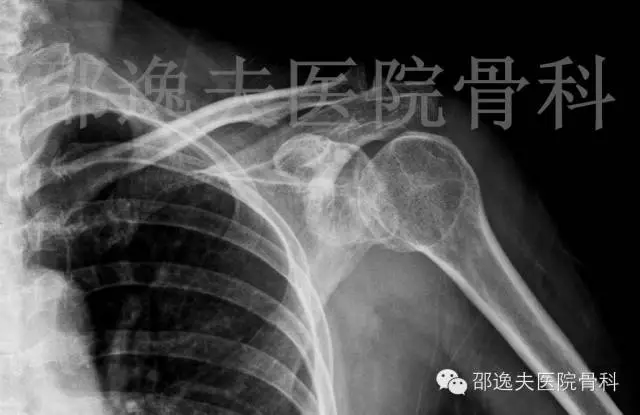

手法复位后X线片

这是典型的骨性Bankart损伤,即指外伤导致肩关节前脱位后与肩关节盂前下缘撞击发生的关节盂前缘撕脱骨折。